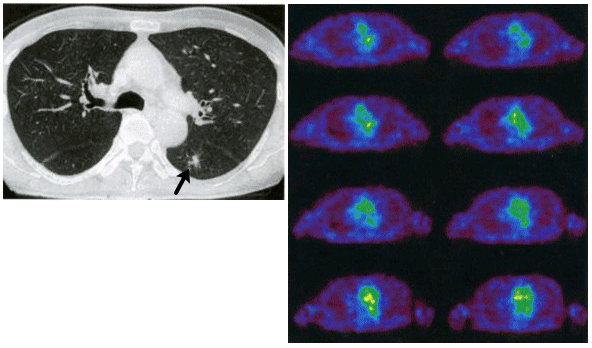

図2は、細気管支肺胞上皮がんの症例で、CTで左肺下葉に小さな腫瘤像が認められる(矢印)が、FDG-PETでは、異常集積を指摘できない。肺がんのFDG-PETは、感度96%、特異度73%、正診率90%と良好であるが、内部に空気を含み、すりガラス様陰影(ground-glass opacity)を示す肺胞上皮がんや高分化型腺がんは偽陰性となることが多い。

図2 細気管支肺胞上皮がんの胸部CT像(左)と、同症例のFDG PET胸部横断像(右)CTで左肺下葉に腫瘍性病変(矢印)が認められるが、FDGの明らかな集積は認められない。(原論文2より引用)